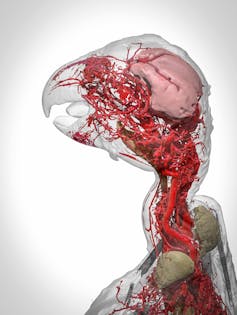

Such explanations are, of course, important. The sheer beauty and complexity of a mouse’s retinal surface – created by Gabriel Luna using confocal microscopy – adds another dimension. But his technique doesn’t just produce beautiful images: confocal microscopy is hugely beneficial to patients because it’s non-invasive. It also enables a better understanding of eye disease and can be shared by researchers across multiple locations.